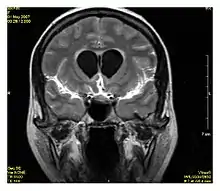

Fluid-attenuated inversion recovery (séquence FLAIR)

La séquence Fluid-attenuated inversion recovery (FLAIR) est une séquence IRM en inversion récupération qui annule le signal des fluides. Cette séquence est généralement utilisée pour l'IRM cérébrale pour supprimer le signal du liquide cérébrospinal (LCS), ce qui permet de mieux observer certaines pathologies, notamment celles présentes à l'interface parenchyme-LCS[1],[2]. La séquence fut développée dans les années 1990 par l'équipe de recherche de Hammersmith (constituée de Graeme Bydder, Joseph Hajnal, et Ian Young[3].